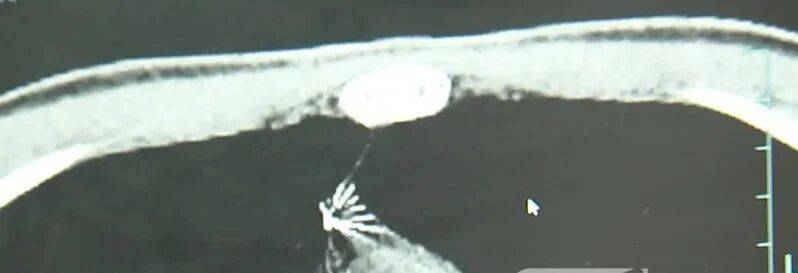

近日,安徽17岁小伙小陆参加征兵体检,胸片结果显示:胸腔内有一处金属高密度影,形态细长,像一根针巨力索具股票。

进一步的CT检查确认,异物是一枚金属针,斜插在肺组织内,位置十分凶险巨力索具股票。

杭州市第一人民医院心胸外科副主任冯兴说:“我们看到这个针的尖锐部,正好指向他体内的一个大血管,边上是上腔静脉和胸主动脉,因此这个针稍有不慎,就有可能造成周边血管的损伤,甚至危及生命巨力索具股票。”